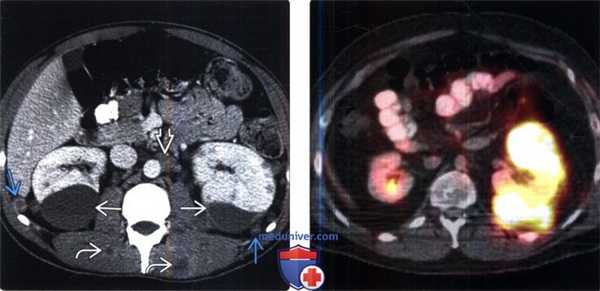

(Слева) КТ с контрастированием, аксиальная проекция: слившаяся околочревная лимфаденопатия вследствие НХЛ.

(Справа) КТ с контрастированием, аксиальная проекция: визуализирована панкреатическая НХЛ в виде массивного образования в области головки поджелудочной железы. Лимфома расположена в перипанкреатической группе лимфатических узлов, однако внешне может имитировать первичную опухоль поджелудочной железы.

(Слева) При аксиальной КТ с контрастным усилением определяются гиподенсные мягкие ткани в виде «кожуры» вокруг обеих почек, классическое проявление периренальной лимфомы.

(Справа) При аксиальной КТ с контрастом определяется большое мягкотканное объемное образование вокруг правой почки, проявление периренальной НХЛ.